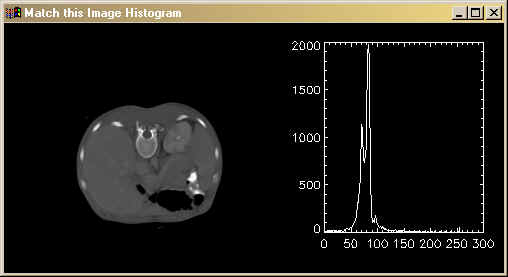

Display it next to its histogram by typing these commands. You see the result below the text.

Window, 0, XSize=500, YSize=250, Title='Match this Image Histogram', XPos=100, YPos=100 !P.Multi=[0,2,1] TVImage, image_to_match Plot, Histogram(image_to_match), Max_Value=5000 !P.Multi=0